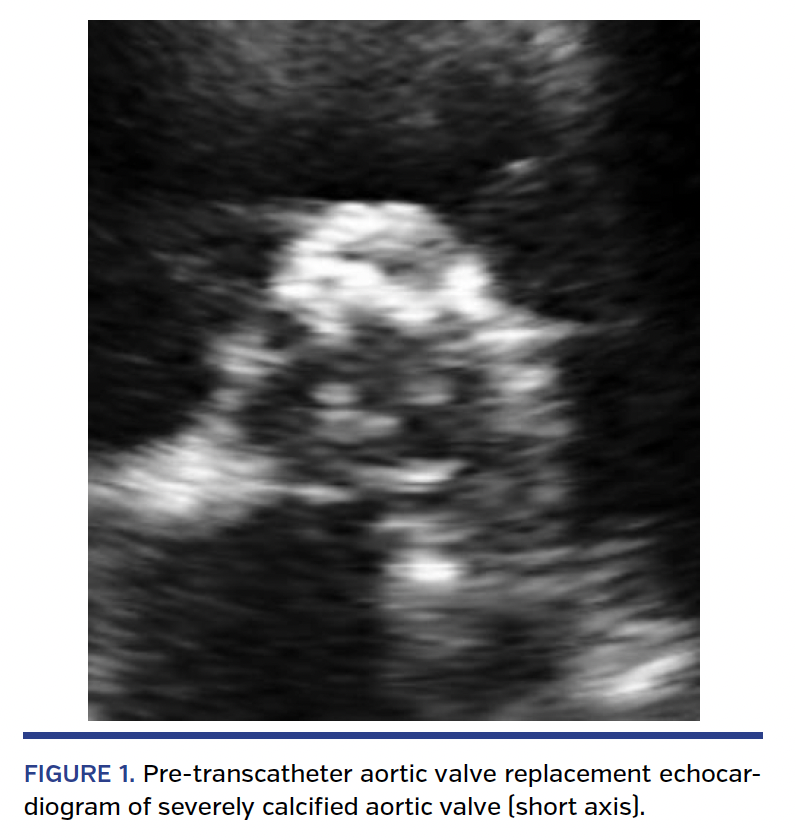

First TAVR. Our representative case was a 76-year-old male with a past medical history significant for non-obstructive coronary artery disease, insulin-dependent diabetes mellitus, end-stage renal disease on hemodialysis, hypertension, chronic obstructive pulmonary disease, and severe aortic stenosis with New York Heart Association (NYHA) class III symptoms. The patient was initially seen in March 2015 at our valve clinic. Physical examination was significant for clinical signs of congestive heart failure (NYHA class III). His lung auscultation revealed bibasilar crackles and cardiac auscultation showed a late peaking systolic ejection murmur grade 4/6 at the apex and left intercostal space. His pre-TAVR echocardiogram showed a heavily calcified aortic valve (Figure 1) and a mean gradient of 40 mm Hg, with a peak velocity of 4.06 m/s. Mild aortic